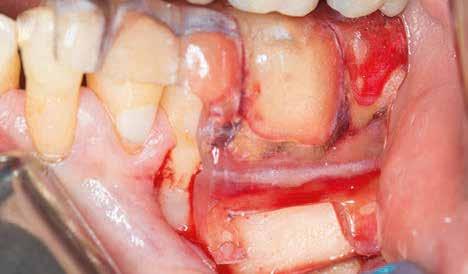

CÉLZOTT ENDODONCIAI MIKROSEBÉSZET

1. a-n. ábrák: Preoperatív CBCT-felvétel a bal alsó 6-os (3.6) fogról. Az axialis (a), coronalis (b) és sagittalis (c) nézeteken a mezialis és distalis gyökerek apicalis harmada körül sugáráteresztő zóna és ép buccalis corticalis csont látható. Egy olyan sablont terveztünk, amely jelezte a csontablak határait az apicalis terület pontos elérése érdekében (d). A mikrosebészeti bevatkozás során a sablont a helyére illesztettük (e), a csontablak határait megjelöltük (f) egy Piezotome CUBE LED kézi-darabba fogott fűrésszel, majd kivágtuk és eltávolítottuk (g és h) az apicalis területhez történő hozzáférés, illetve a mezialis és distalis gyökerek rezekciójának, retrográd preparációjának és retrográd gyökértömésének elvégzése érdekében (i). Végezetül a csontablakot visszaillesztettük és kollagén szivaccsal stabilizáltuk (j). A műtét után közvetlenül készített röntgenfelvétel a 3.6-os fogról (k). A kétéves kontroll során készített CBCT-felvétel: axialis (l), coronalis (m) és sagittalis (n) nézetek.

Esetbemutatás (1.)

Egy 63 éves páciens korábban már kezelt bal alsó első nagyőrlőfogából (3.6) eredő mérsékelt fájdalom miatt kereste fel rendelőnket. A kórtörténetében panasza szempontjából releváns információ nem szerepelt. Az elkészült CBCT-felvételen a korábbi kezelések során észre nem vett, jelenleg feltáratlan meziobuccalis csatornát, valamint a mezialis és distalis gyökerek körül kialakult periapicalis elváltozást, és ezt a léziót borító intakt buccalis corticalis csontlemezt láttunk.

A fog revideálását és újbóli gyökértömését két ülésben végeztük el. A régi gyökértömés eltávolítását, valamint mindhárom gyökércsatorna megmunkálását és fertőtlenítését követően kalcium-hidroxid alapú gyógyszeres zárást helyeztünk a gyökércsatornákba. A gyökértömés egy héttel később került behelyezésre. A páciens panaszai két hónap elteltével sem szűntek.

Klinikai vizsgálat során vertikális kopogtatási érzékenységet jelzett. A fog körül mérhető szondázási mélység és a fogmobilitás fiziológiás volt. A CBCT-felvételen nem észleltünk a csontos regeneráció megindulására utaló jeleket (1. a–c. ábrák). A korábban gyökérkezelt, gyökértömött és revideált 3.6-os fog esetében az alábbi diagnózis került felállításra: periodontitis periapicalis symptomatica. A panaszokat okozó fog további ellátása során navigált endodonciai mikrosebészetet kívántunk alkalmazni. Az alsó állcsontról intraorális szkent (TRIOS, 3Shape) készítettünk, és a felszíni topográfiát tartalmazó STL fájlt, valamint a CBCT-felvétel készítése során nyert DICOM fájlokat a Blue Sky Bio szoftver segítségével egyesítettük. A sebészi sablon megtervezésére az így kapott háromdimenziós képet használtuk. A sablon kialakítása során arra törekedtünk, hogy a sablon egyértelműen meghatározza a gyökércsúcsi terület eléréséhez szükséges csontablak határait (1. d. ábra)

A beavatkozás során helyi érzéstelenítésben teljes vastagságú mucoperiostealis lebenyt képeztünk, és a sablon segítségével bejelöltük a preparálandó csontablak határait. Az ablak széleinek megfelelően Piezotome CUBE LED kézi-darabbal (ACTEON) a kortikális teljes vastagságában vágást ejtettünk, majd az így kapott csontlemezt (ablakot) eltávolítottuk (1. e–h. ábra), és ezt követően steril fiziológiás sóoldatba helyeztük. A rezekció elvégzését követően (1. i. ábra) a mezialis csatornákat ultrahangos eszközök segítségével (NSK) retrográd irányból preparáltuk, majd az így kialakított mélyedésbe retrográd gyökértömést készítettünk. A tömés anyagául az EndoSequence BC RRM Fast Set Putty-t (Brasseler) választottuk. A tömés elkészítését követően a csontablakot visszaillesztettük, és a stabilizálása érdekében a vágásoknak megfelelően kialakult résekbe kollagén szivacsokat (Collagen Tape, Zimmer Biomet) helyeztünk (1. j-k. ábra). A lebenyt 6/0-s Prolene varratokkal (Corpaul) rögzítettük.

A kétéves kontroll során elvégzett klinikai és radiológiai vizsgálat (CBCT-felvétel) a periapicalis elváltozások megszűnését és a corticalis csontállomány tünet- és szövődménymentes gyógyulását